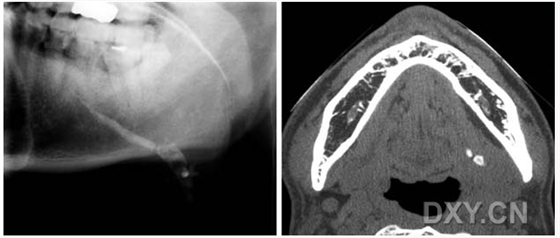

涎石病

球狀上頜囊腫

含牙囊腫

球狀上頜囊腫    含牙囊腫